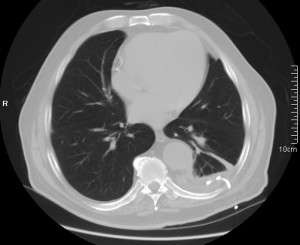

Informe TC: colección líquida periférica encapsulada con aire en su interior y de morfología redondeada.

Diagnóstico final: EMPIEMA PLEURAL.

La solución terapéutica del empiema es la colocación de un tubo de drenaje pleural. El empiema tiene que drenarse siempre ne su totalidad. En las siguientes imágenes se observa el tubo colocado y cómo la colección ha disminuido.